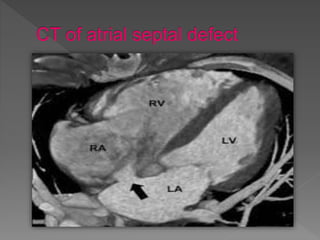

An atrial septal defect is a congenital heart defect where a hole exists in the wall separating the two upper chambers of the heart, the atria. This allows oxygen-rich blood from the left side of the heart to mix with oxygen-poor blood from the right side. This mixing of blood can lead to lower than normal oxygen levels in blood flowing to the brain, organs, and tissues. However, a small atrial septal defect may not produce noticeable symptoms. Multiplane transesophageal echocardiography can be used to image a moderate-sized atrial septal defect between the two atria.